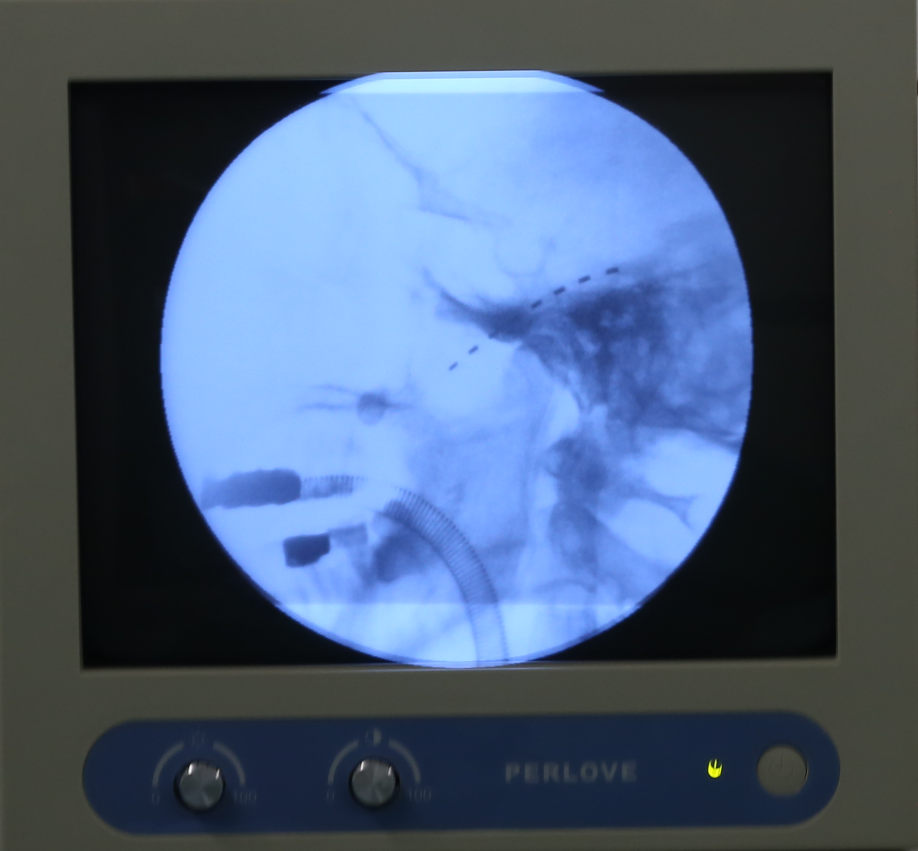

11月27日,四川省人民医院赵冬冬主任联合麻醉手术科,为李大爷实施了院内首例三叉神经半月节电刺激装置植入术。术中X线透视下精确定位,精准穿刺,将电极置入三叉神经节附近,X线透视可见电极置入位置准确,且未出现并发症,手术微创、无痛、安全、有效。

术后,患者通过调整电刺激装置,电流覆盖患者疼痛区域90%,疗效显著。经过医生多次调适,李大爷表示平常疼痛难忍的地方,现在是酥麻的感觉,已经感觉不到疼痛,夜间可安稳入睡,手术圆满完成。待电刺激治疗达到疗程后,拔除电极,李大爷就可出院。